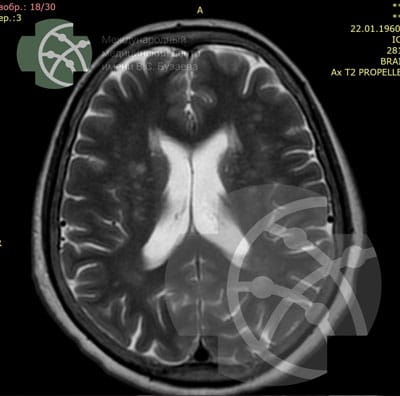

T2 axial / 4 мм

Our brain MRI protocol includes the following programs:

Program / slice thickness

3D T1 sagittal / 1 мм

T2 FLAIR axial / 4 мм

DWI* axial / 4 мм

SWAN** axial / 3 мм